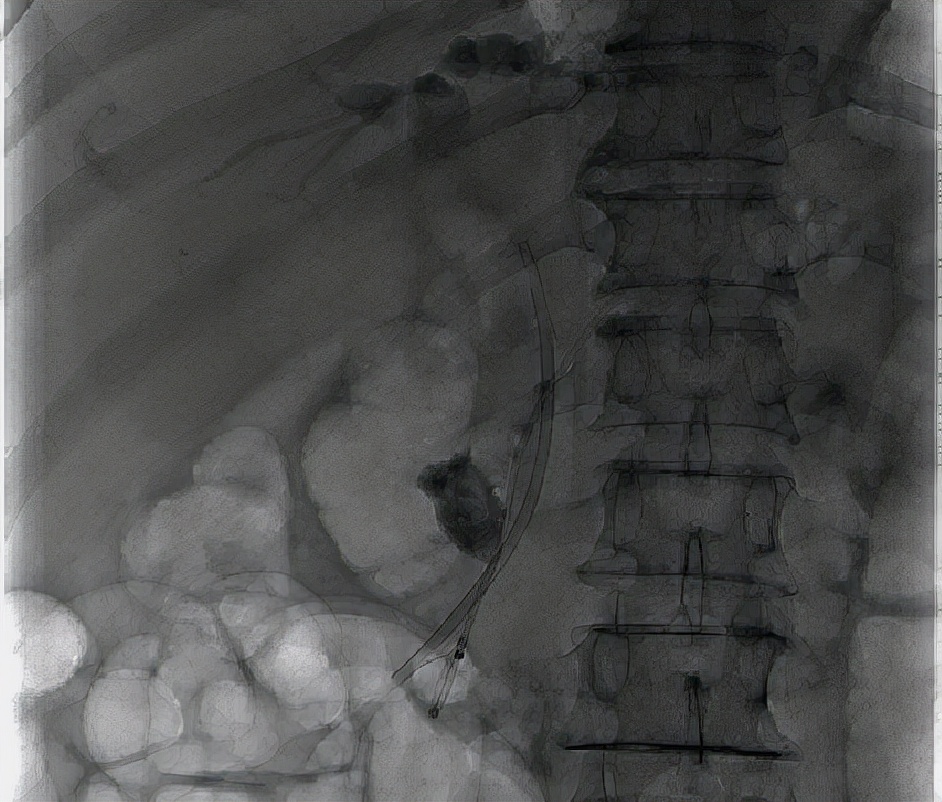

手术过程中,章诺贝教授在经内镜下对胰管插管造影后发现胰管起始部见数个大小不等的充盈缺损影,最大者为23mm*15mm。胰管内的巨大结石,这无疑为手术加大了难度。紧急情况下,手术团队决定施行乳头小切开,经反复对胰管进行扩张后,顺利越过梗阻部位至远端胰管并置入胰管支架,胰液引流通畅并见较多蛋白栓子随胰液流出,同时在胆管置入胆管支架,大量墨绿色胆汁通过胆道支架流出,手术十分成功,术后患者恢复良好。

ERCP的中文名称叫内镜下逆行胰胆管造影,是通过十二指肠镜进入十二指肠,找到十二指肠乳头,也就是胆管和胰管排泄胆汁和胰液的开口处,然后进行插管。造影可使胆管和胰管在X线下显影,从而检查胆管或者胰管内的病变。起先是一种检查手段,但随着技术的逐步成熟,现在已经被广泛应用于检查和治疗胆胰疾病,如胆总管结石、胰管结石或者胆道梗阻,包括各种原因引起的胆道梗阻需要引流的患者。